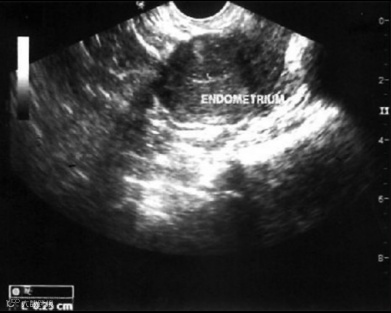

研究过程中,科学家们将1000万个(1×10^7个)脐带来源的间充质干细胞附着在胶原支架上,并在成功解除宫腔粘连后,将装载有干细胞的支架植入患者宫腔内。随后对所有受试者进行了为期3个月的严密随访,以详细监测子宫内膜厚度、宫腔粘连程度评分以及与子宫内膜再生相关的分子标志物变化。

研究结果表明,在接受UC-MSCs移植干预后,未观察到与干预直接相关的严重不良事件发生。经过3个月的干预及随访,患者的平均子宫内膜厚度相较于干预前有了显著增加,同时宫腔粘连的评分也有所下降。组织学分析进一步揭示,在干细胞疗法干预后,患者子宫内膜的增殖活性、分化状态以及新生血管形成能力均得到了积极改善。

患者干预前后超声对比